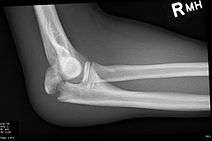

Frontal and lateral X-ray views of the elbow are typically done to investigate the possibility of an olecranon fracture. A standard lateral view of the elbow insufficient to diagnose olecranon fractures. A true lateral x-ray is essential to determine the fracture pattern, degree of displacement, comminution, and the degree of articular involvement.